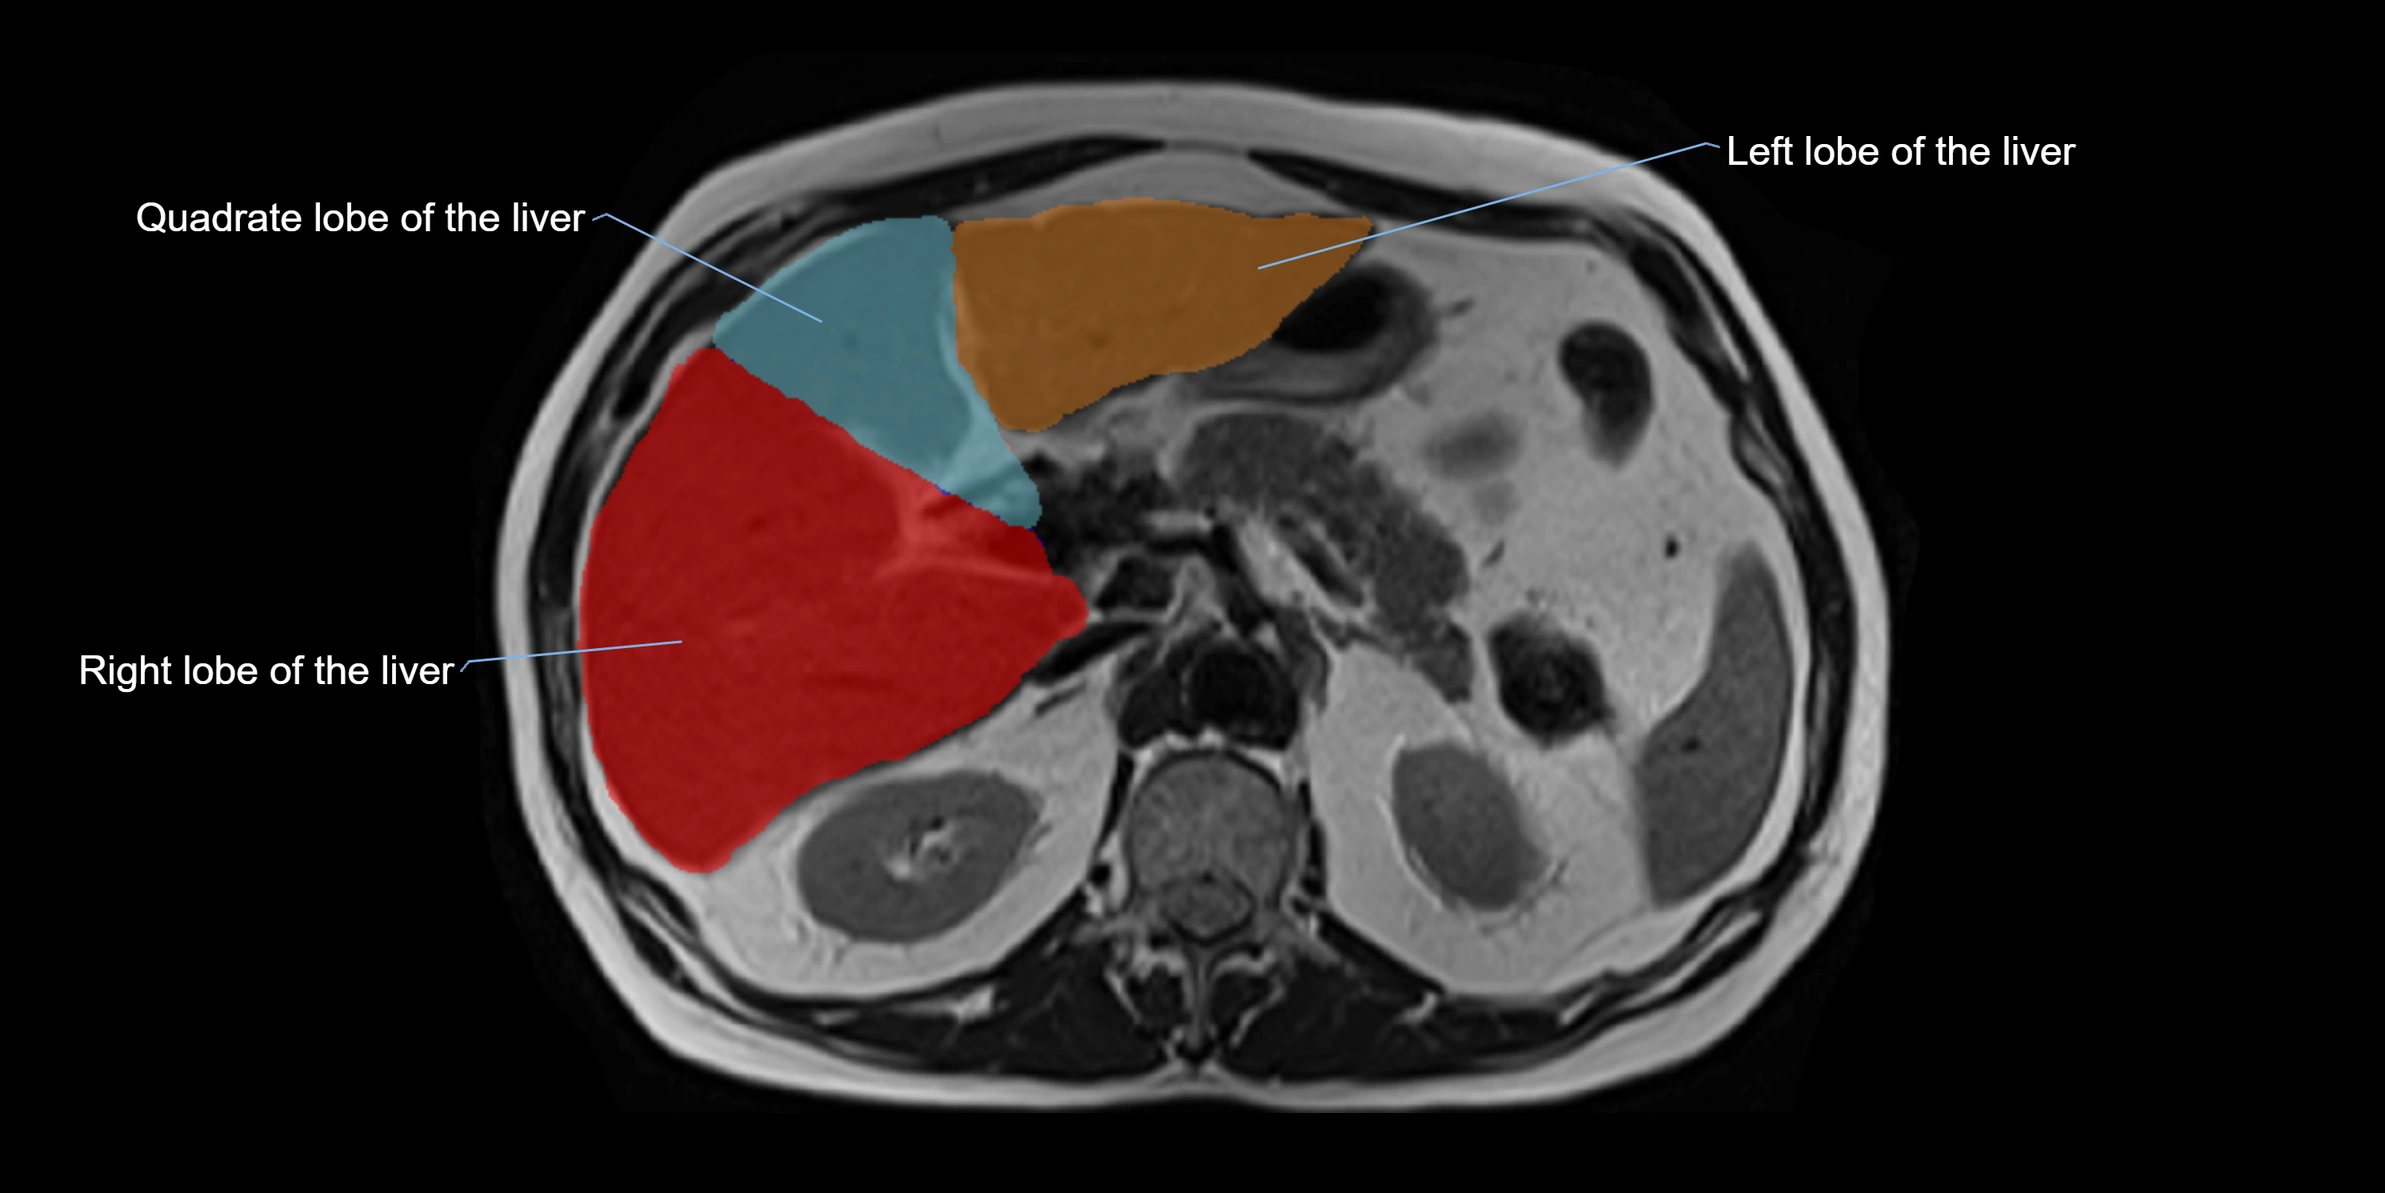

MRI image

image